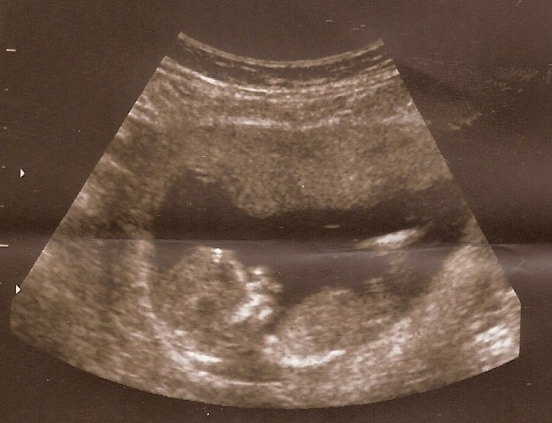

Hol is kezdjem, hazajövetelünk utáni 2. héten elkezdtem nagyon szédülni és folyamatos szívritmuszavarom lett. Annyira gyengének éreztem magam, és folyamatosan nem kaptam levegőt+halálfélelmem volt, annyira félrevert, hogy felhívtam az egyik barátnőmet aki a kardiológián dolgozik, hogy ugyan már nézzen meg valaki, mert valami nem stimmel. Szóval bementem, néztek EKG-t, vettek vért és megnézték a szívemet uh-on, mert van olyan, hogy terhesség utáni szívizom elfáradás, mivel 9 hónapig meg van terhelve, így előfordul, hogy szülés után megzavarodik.

EKG jó lett, uh-on sem láttak semmit. Dr-nő mondta, hogy szerinte a stressz a megváltozott helyzet miatt(4 gyerek), a fáradság és kialvatlanság okozza a ritmuszavart. Ehhez még hozzájárul a 2 fiú kiskamaszkori viselkedése. Folyamatosan mérgelődök velük, mert semmit nem hajlandóak úgy csinálni ahogy kérem őket.Azt is mondta, hogy pihenjek sokat(ha-ha-ha-ha).A vérképem is egész jó lett, kivéve a koleszterinem mutatott emelkedett értéket, szóval mostantól a zsíros dolgokat hanyagolnom kell.